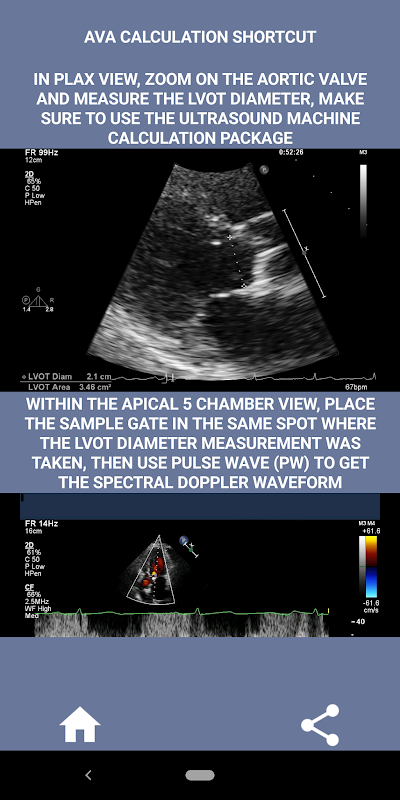

Theo tôi, nếu một người được phỏng vấn có thể thể hiện rõ kỹ năng này thì người đó có lợi thế rất lớn so với những ứng viên còn yếu trong lĩnh vực này (điều đó cũng hợp lý vì bình thường có rất nhiều trường hợp hẹp eo động mạch chủ). Nếu bạn đang ứng tuyển vào vị trí bác sĩ siêu âm tim, một người chỉ cần nâng cao kỹ năng của mình hoặc một sinh viên tiếng vọng, thì ứng dụng này được thiết kế cho bạn trong tâm trí của một bác sĩ siêu âm tim đang thực hành. Đơn giản và ngắn gọn, đúng trọng tâm với nhiều video minh họa chỉ ra chính xác vị trí cần đo (ví dụ: đường kính LVOT) và cách đo theo hướng dẫn ASE / ICAEL đã xuất bản.